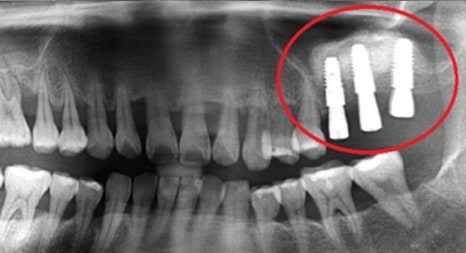

위 턱뼈는 아래턱뼈보다 얇고 코와 뺨 사이 빈 공간 (상악동)이 있어서 임플란트를 식립할 경우 실패 가능성이 높아집니다.

부족한 뼈를 보충하기 전 상악동 거상술을 시행할 때 노하우가 부족하면 임플란트 식립 후 쉽게 빠져버리거나 입 천장 쪽에 천공이 나는 부작용이 생기기 때문에 치과 진료 중 난도가 높은 과정에 속합니다.

본 환자분은 부족한 잇몸뼈를 보충하는 뼈 이식술과 난도 높은 상악동 거상술을 진행해 안정적인 임플란트 수술을 마쳤습니다.

연세고운미소치과 목동점 문원규 박사 (대표원장)는 턱뼈의 해부학적 구조를 충분히 고려하여 임플란트 수술을 해온 노하우를 바탕으로 상악동 거상술을 비롯한 난도 높은 수술을 안정적으로 진행하고 있습니다.